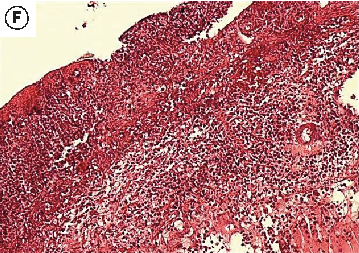

Figure 7

The Healing Effect of Aloe Vera Gel on Acetic Acid-Induced Ulcerative Colitis …